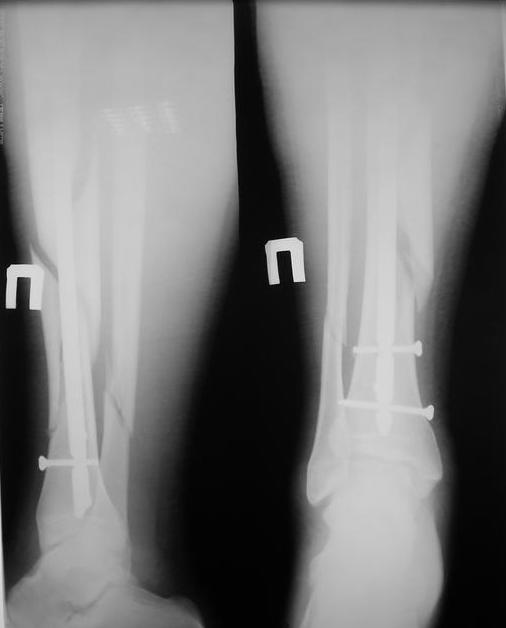

У нас был молодой пациент М.(26лет), травма 25 января 2009г, катался на лыжах и получил травму. Поступил к нам в отделение в экстренном порядке. При обследованиии выявлен закрытый винтоообразный оскольчатый перелом правой большеберцовой кости и косой перелом малоберцовой кости на границе средней и нижней трети. Выполнен интрамедуллярный блокируемый синтез большеберцовой кости, оси и длина конечности восстановлена. После операции пациент ходил с полной нагрузкой. Через 3 месяца на контрольных рентгенограммах сращения нет, динамизации не выполняли, так как оскольчатый перелом.(снимки в динамике прилагаются). Посоветуйте, что в данном случае делать наиболее целесообразно?

Остеосинтез, похоже, сделали с перерастяжением, так что динамизировать, наоборот, надо было еще и раньше обычного, недели через 4 после операции.

Да есть диастаз, но скорее от смещения осколка по ширине, а не по длине - по малоберцовой длина нормальна.

И малоберцовая перерастянута. По большеберцовой видно щель по переднему контуру, промежуточный фрагмент к этой области не имеет отношения.